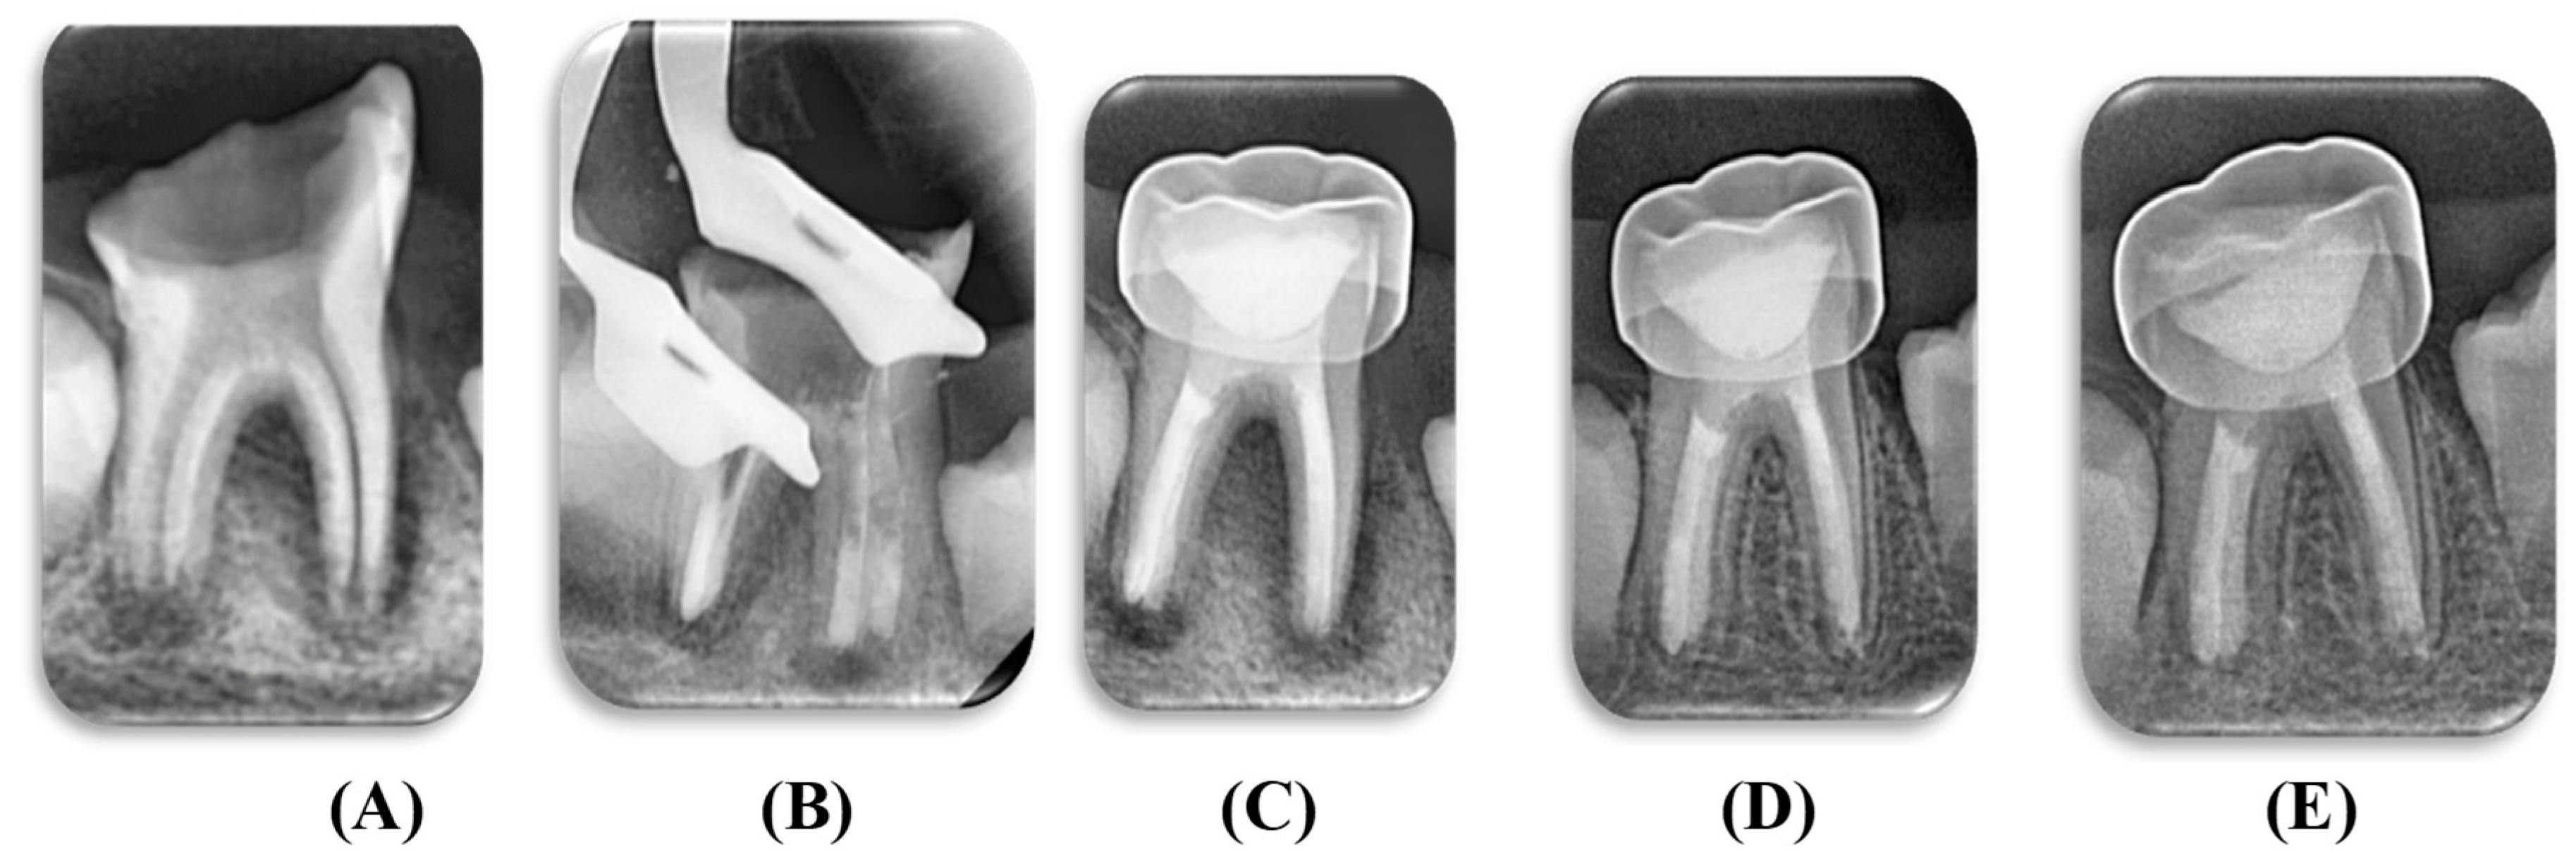

2.7. Clinical Procedures

2.9. Filling of the Root Canals

2.10. Coronal Restoration

2.11. Clinical and Radiographic Evaluations